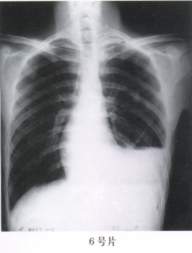

6.(6号片)此片有哪些异常?

A、左侧液胸

B、左侧气胸

C、左侧胸膜炎胸腔积液

D、左肺囊肿

E、左肺不张

答案:1—6:EDACAC 15—20:ACBDED